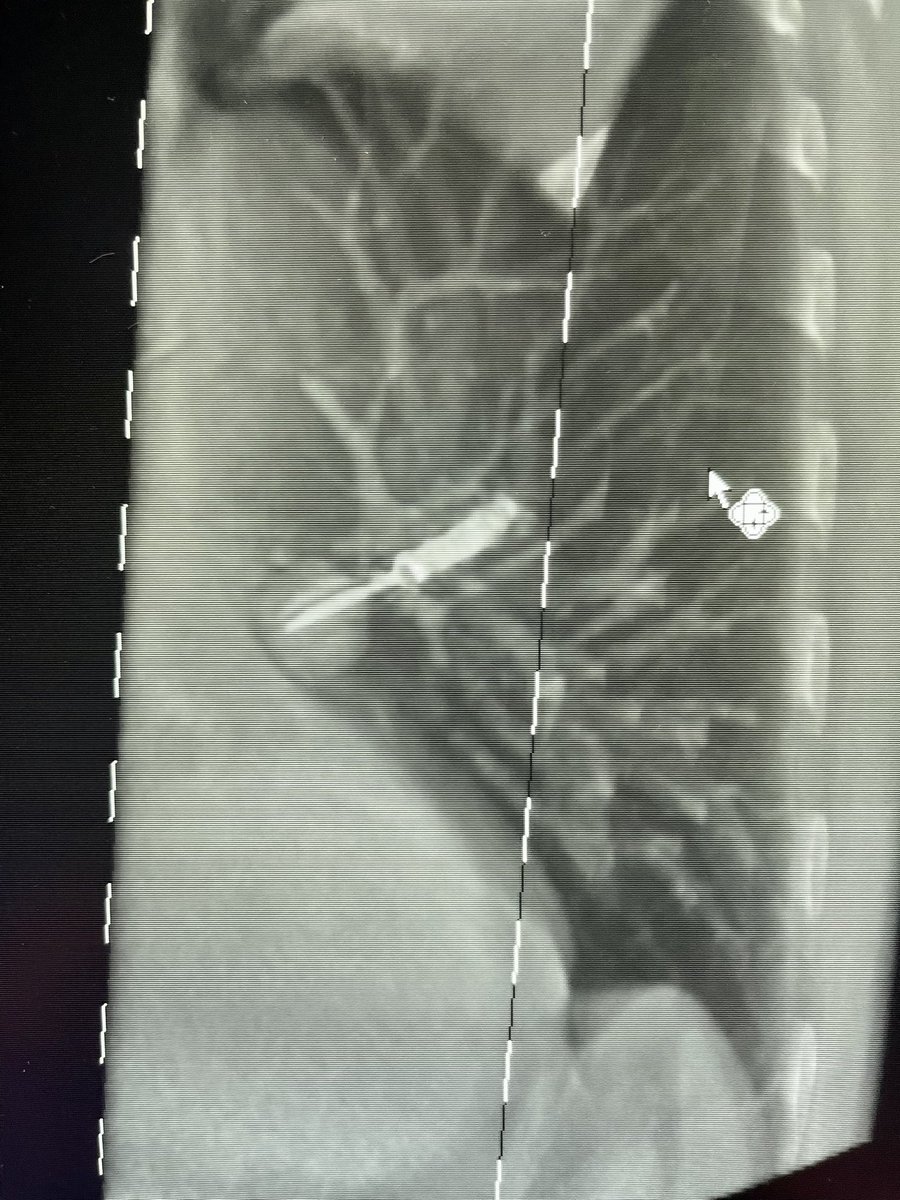

Bhadra & Condra CBCT Bronchoscopy

If you don't like the road you are on, pave a new one: Cone Beam CT Bronchoscopy.